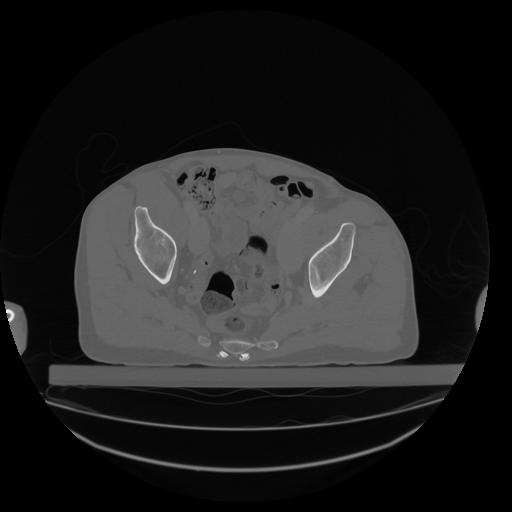

34 CUERPO,CE,Vol,1.0,CUERPO,,